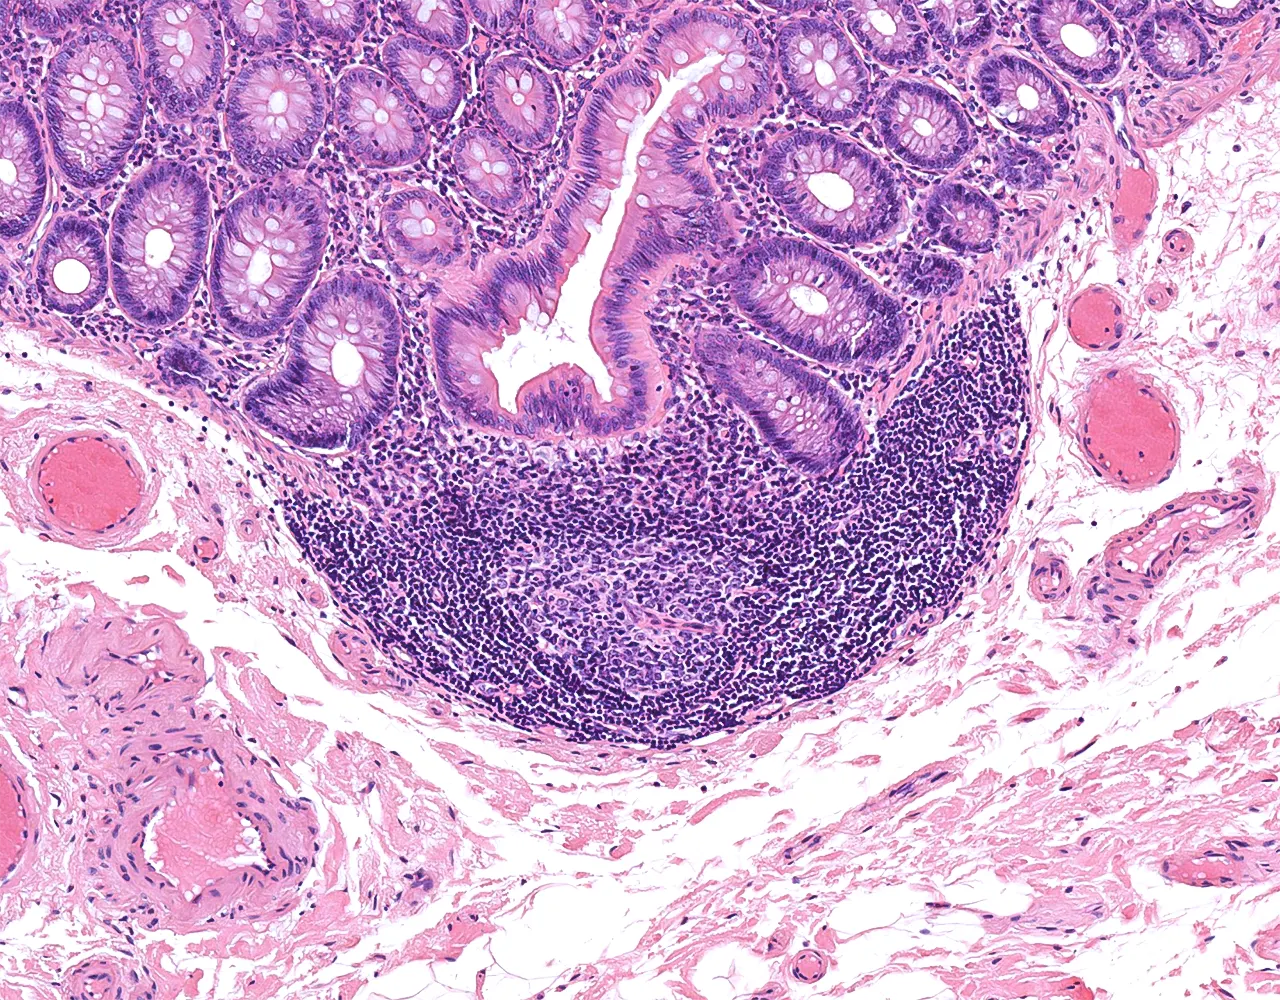

- L’appendice est un diverticule borgne naissant du caecum.

- Il contribue principalement à la fonction immunitaire locale grâce à son abondant tissu lymphoïde et peut également agir comme réservoir du microbiote intestinal normal.